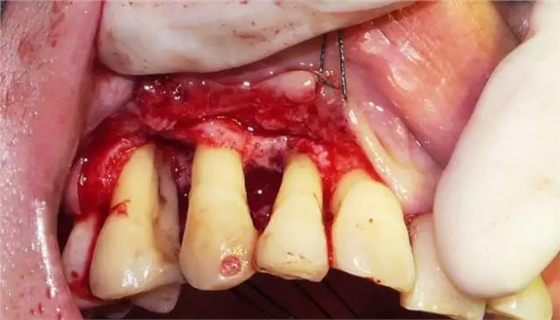

翻開頰側粘骨膜瓣,牙石沒有了但是還有大量的肉芽組織

這張圖片是去除肉芽組織之后的圖片,我們看到右上五的近中面還有一條黑色的牙石存在,這是三次齦下刮治后遺留下來的牙石,由此可見,對于重度牙周病僅僅靠齦下刮治是無法徹底清除齦下牙石的,牙周手術治療還是非常有必要的。

術中徹底清除后的牙根面

翻開腭側粘骨膜瓣,去除炎性肉芽組織,根面用牙周銼清理后,顯示明顯的骨下袋和干干凈凈的根面。在這樣的骨下袋里植骨效果是非??煽康?。